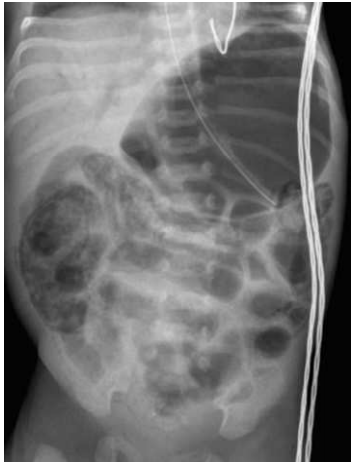

A enterocolite necrosante (NEC), mostrada na figura abaixo, é uma doença de origem desconhecida que afeta principalmente recém-nascidos prematuros (80% dos casos). As manifestações cobrem amplo espectro, de distensão abdominal leve com hematoquezia a choque séptico fulminante com necrose transmural de todo o trato gastrointestinal. Com relação a essa patologia, analise as afirmativas a seguir.

enunciado 1921720-1

http://www.adhb.govt.nz/newborn/TeachingResources/Radiology/AXR/NEC/NECwithPortalGasAP1.jpg

1) Ocorre tipicamente em recém-nascidos com uma idade gestacional corrigida de 30-32 semanas, um momento em que a maioria dos prematuros está em progressão de dieta enteral.

2) O leite materno pode reduzir o risco de NEC. Uma das ações seria favorecer o crescimento de Lactobacillus bifidus, promovendo o desenvolvimento de um microbioma intestinal saudável.

3) O estagiamento da NEC é realizado com base em sinais sistêmicos e radiológicos.

4) O tratamento deve ser conservador, apenas com vigilância rigorosa e antibioticoterapia nos casos de pneumoperitônio, devido à instabilidade clínica e a gravidade do paciente.

5) A ausência de NEC intrauterina sugere uma necessidade absoluta de colonização intestinal em sua patogênese.

Estão CORRETAS: